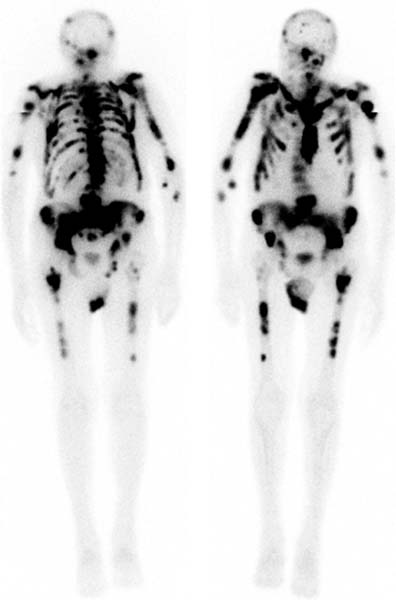

Bone Scans

Advantages of Bone scans over Conventional Imaging:

Early detection of bone metabolism changes, whole body screening

3 Phase Bone Scan: blood flow, blood pool, delayed.

Used for: osteomyelitis, prosthesis infection

SPECT/CT Benefits

SPECT: a nuclear medicine imaging technique that creates detailed, 3D images of organs, tissues, and bones by detecting the gamma rays emitted by radioactive tracers injected into the body

Benefits:

Combines function and structure so improved localisation

Superscan

Intense skeletal uptake with reduced renal/ST activity (eg: metastatic disease)

Common Indications:

? bony mets

Infection

Trauma

Arthritis